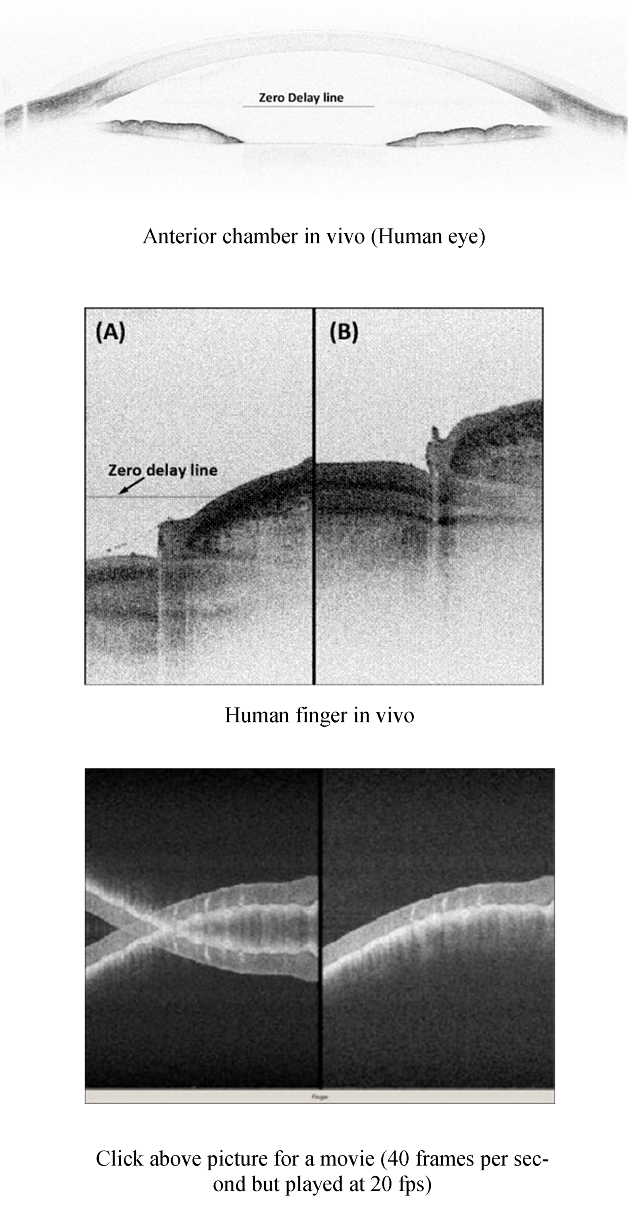

In vivo 3D Full Range Complex Fourier Domain OCT Imaging

Human eye anterior chamber (6.6 MB)

In vivo 3D Imaging of Human Skin (Finger Pad)

3D sweat glands.avi (16.5 MB)

En-face palm skin.avi (25.8 MB)